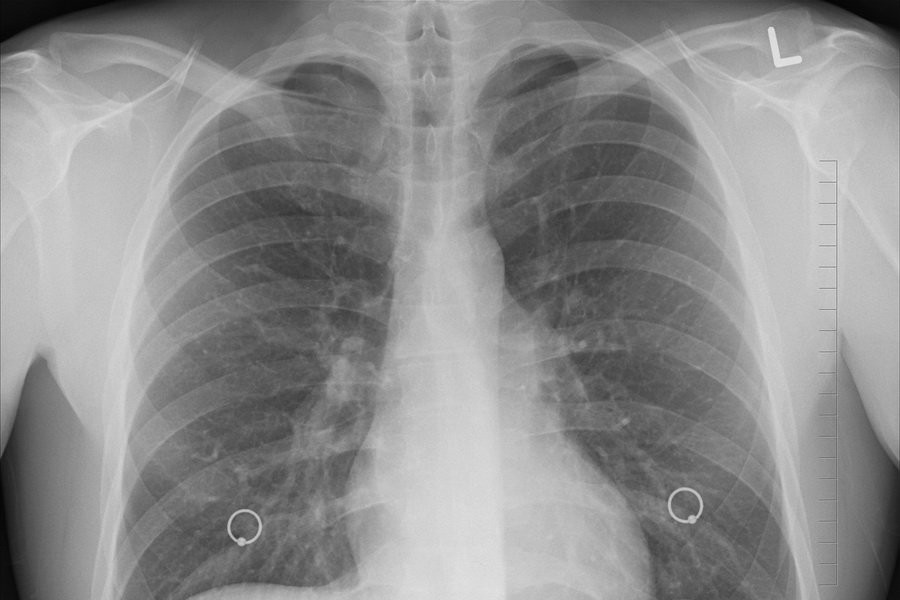

Рак легких остается одной из ведущих причин смертности во всем мире, ежегодно унося жизни 1,8 миллиона человек. Курение табака является главным фактором риска, вызывая около 85% всех случаев заболевания. В попытке найти эффективное решение этой проблемы, исследователи предложили радикальный подход – запрет продажи табачных изделий людям, родившимся между 2006 и 2010 годами.